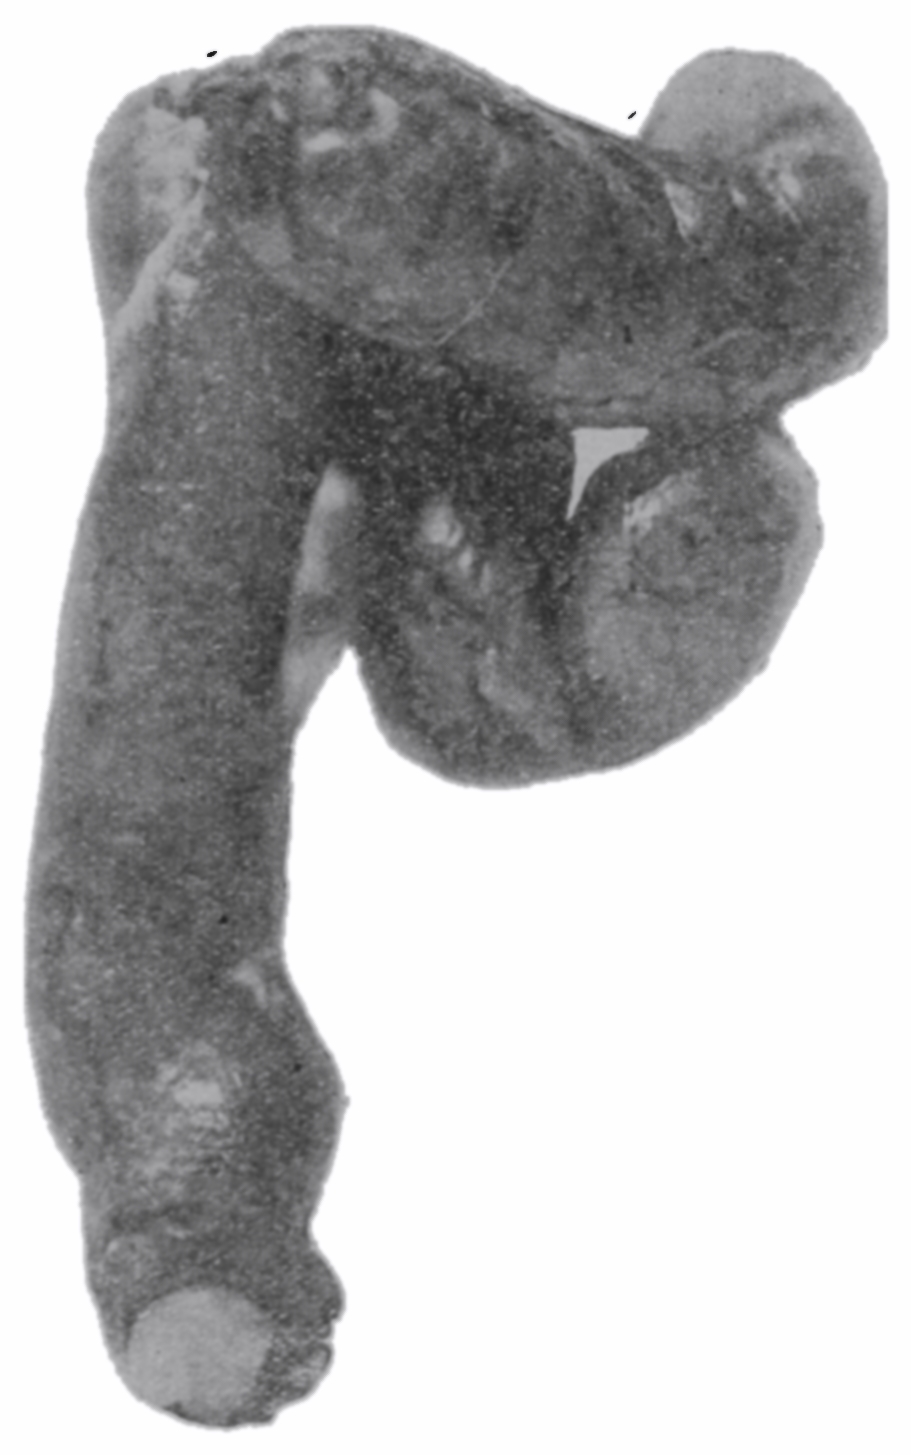

The photographic reproductions here published are documentary evidence of the existence of the obstructions under discussion. The sketch, Fig. 33, which was drawn from the valve while under the microscopic lens, exhibits the character of these obstructions and proves it that of a typic anatomic valve, and the absence of permanent bands of any other character in this organ is evidence that the semilunar valves and the so-called plica transversalis recti, Falten des Rectums, sphincter ani tertius, superior sphincter, and detrusor fecium muscles are one and the same thing and this thing is essentially a valve. It is most prominent when the gut is most distended.